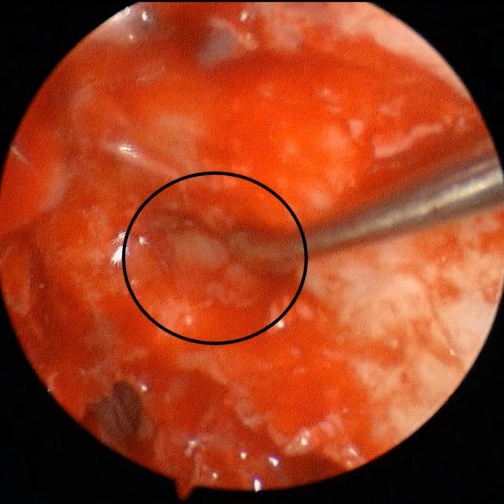

面对这个难题,徐赫医生展现出他的“巧思”:利用鼻腔部位肿物切除时需切除“钩突”组织,亲手制作了一个包含骨质和黏膜的复合组织修复瓣。

“这可以说是一种‘就地取材、变废为宝’的思路。”徐赫医生解释道,“我们将这个修复瓣巧妙地移植到鼻骨的缺损处,让带有骨质的一面朝外支撑起鼻梁,黏膜的一面朝向鼻腔内,完美地重建了鼻部的骨性结构和鼻腔黏膜的完整性,为鼻部外观的恢复奠定了坚实的基础。”